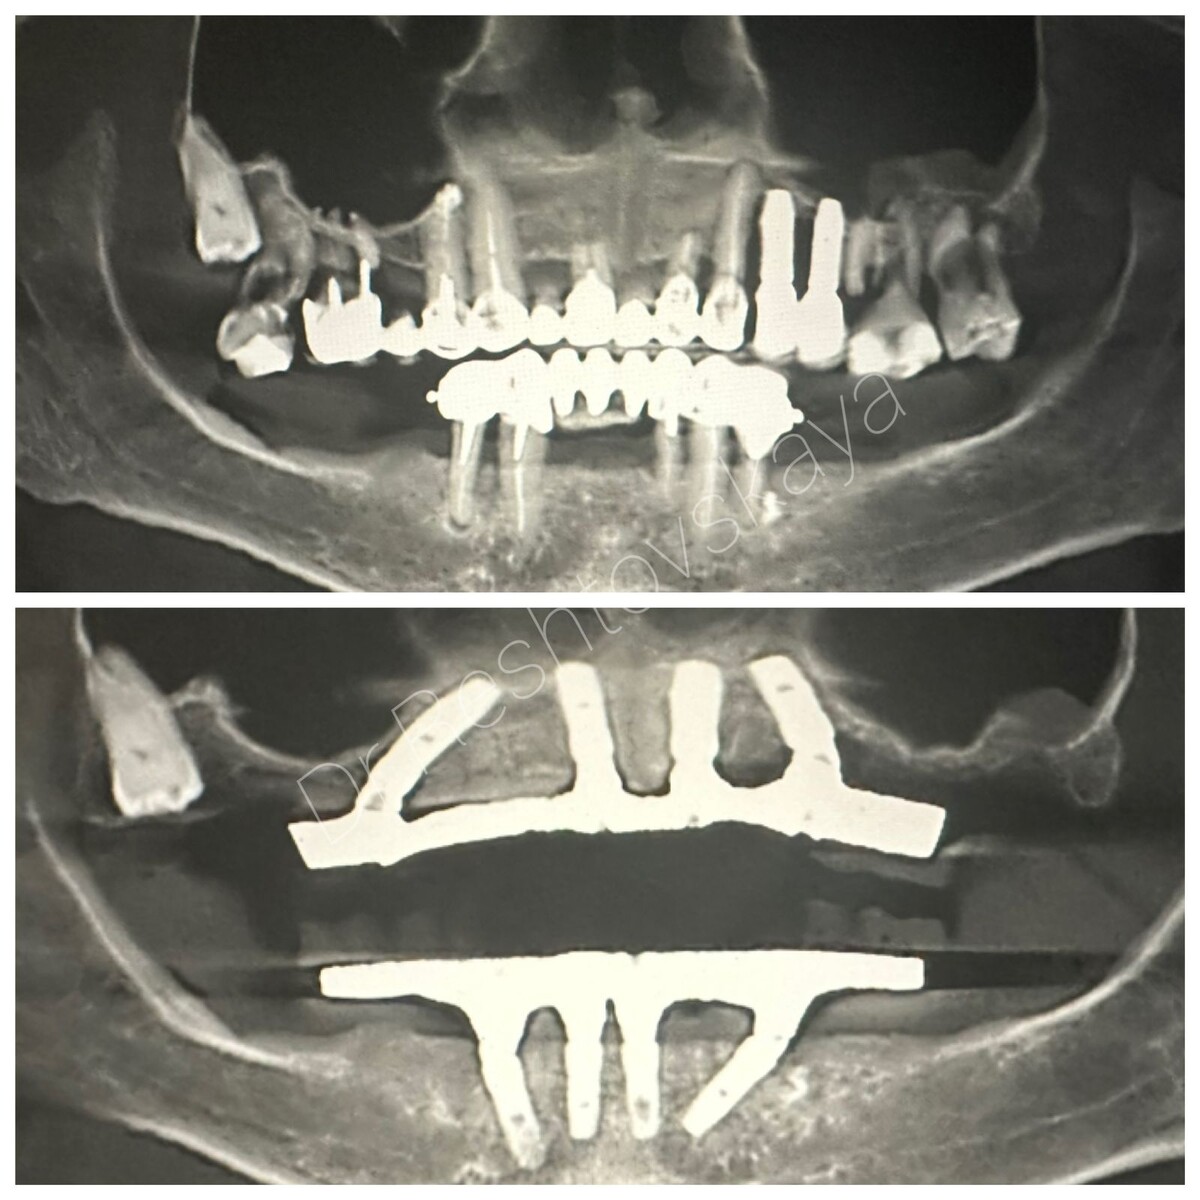

СЛУЧАЙ ИЗ ПРАКТИКИ

Пациентка обратилась к К.Б. Рештовской с жалобами на несостоятельность имеющихся ортопедических конструкций. Была проведена установка 8 имплантатов, установлен протез.